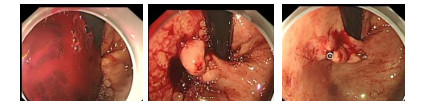

2 结果 2.1 CTP与胃镜表现CTP均提示有肝硬化,52均存在食管胃底静脉曲张,其中单纯食管静脉曲张12例,单纯胃静脉曲张6例,CTP提示食管静脉曲张造影剂外溢6例,与胃镜检查结果一致。胃镜考虑食管胃底静脉曲张(esophagogastric varices,EGV)破裂出血45例,其中食管静脉曲张发现出血或血栓头36例,距门齿28 cm以上2例,28~32 cm 13例,32 cm至齿状线21例,3个位置比较有显著性差异(P < 0.05),胃底静脉曲张发现出血或血栓头9例(其中食管胃底均发现出血或血栓头3例);门高压性胃病(portal hypertensive gastropathy,PHG)出血4例,消化性溃疡(peptic ulcer,PU)出血3例,其中胃溃疡出血2例,十二指肠球部溃疡出血2例。CT提示胃腔大量血液残留22例,16例在常规左侧卧位胃镜操作无法暴露出血病灶,由于有大量血凝块与食物残留,采用改变体位的方法暴露病灶后给予有效止血处理。(见图 1、图 2)。

| 图 2 胃镜操作常规左侧卧位无法暴露出血病灶,采用改变体位的方法暴露病灶,金属夹有效限流后组织胶曲张静脉内栓塞止血 |